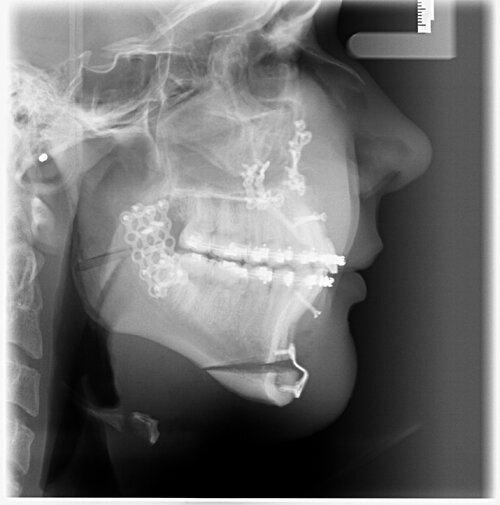

Bimax yesterday

My maxilla was moved from 79⁰ to 82.3⁰ or Sum like that probably bcs of that

I had Bimaxsurgery + genioplasty yesterday performed by Dr Dr Kater, Frankfurt am Main, Germany. I'm 17 and it went well, no nerves are botched and he told me the Plan was executed perfectly fine. In the pictures you can see 24h before and 24h after the surgery. He did a great job with my maxilla and mandible but the genioplasty is slightly underadvanced. My nose had a very big glowup but it'll all look different in 5 months i'm very bloated rn. What do yall think?

Mirin, ur nose bump is already gone I also have similar case like u and also have short face syndrome but am confuse if getting CW rotation will make me more recessed, in ur x ray i can see u wont have a major change in ur face apart from ur nose bump, ramus and chin , i think u will need more osteotomy to get the perfect length of the bone just like LL surgery where they increase ur bone length everyday. Honestly am not aware abt this i will have to research myself abt that cuz gettin a CW rotation will do more harm to face than good it make ur face long and recessed

i had a very very very minimal cw, not optimal for forward growth but there's hardly any surgeon in germany that does cw and i had short face syndrome so it would't ascend me that much. my nose lips and chin look far better i can already see my ramus through the swelling, i'm very happy, but youre right: I didn't get that much sagittal movement, still a good bimax tho